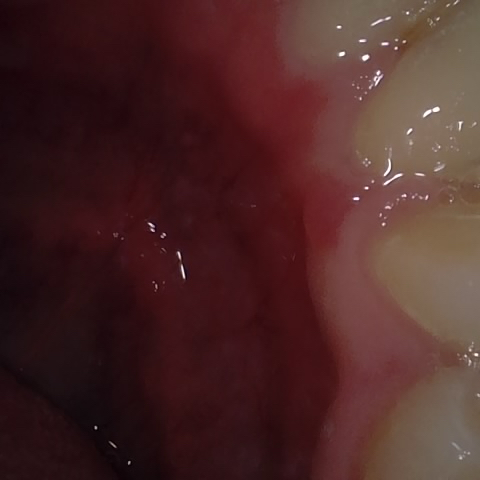

NHD20738

Annotated as "Bad"

Original Image Rendering Image